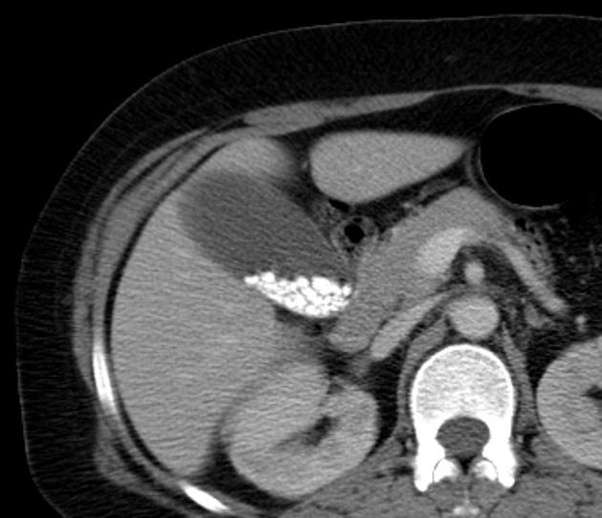

Ct Scan Gallstones. The study shows that the presently used ct scan of the gallbladder is not sensitive enough to select gallstone patients for medical dissolution treatment. While it is known that early generation ct scanners often detect gallstones, the detection rate of newer equipment is not widely known.

Most all gallstones are invisible on ct scan. Especially if they are trapped near or around your billary ducts. Ct scans are often done in an emergency to diagnose severe abdominal pain.

Ct scans can show gallstones, or complications such as infection and blockage of the gallbladder or bile ducts. In addition to detecting gallstones, ct scans can also detect magnetic resonance imaging (mri). A ct scan may be carried out to look for any complications of gallstones, such as acute pancreatitis.

Ct scans are often carried out in an emergency to diagnose severe abdominal pain. However, ct scans also can miss gallstones that you may have. Download as powerpoint open in image viewer figure 4.